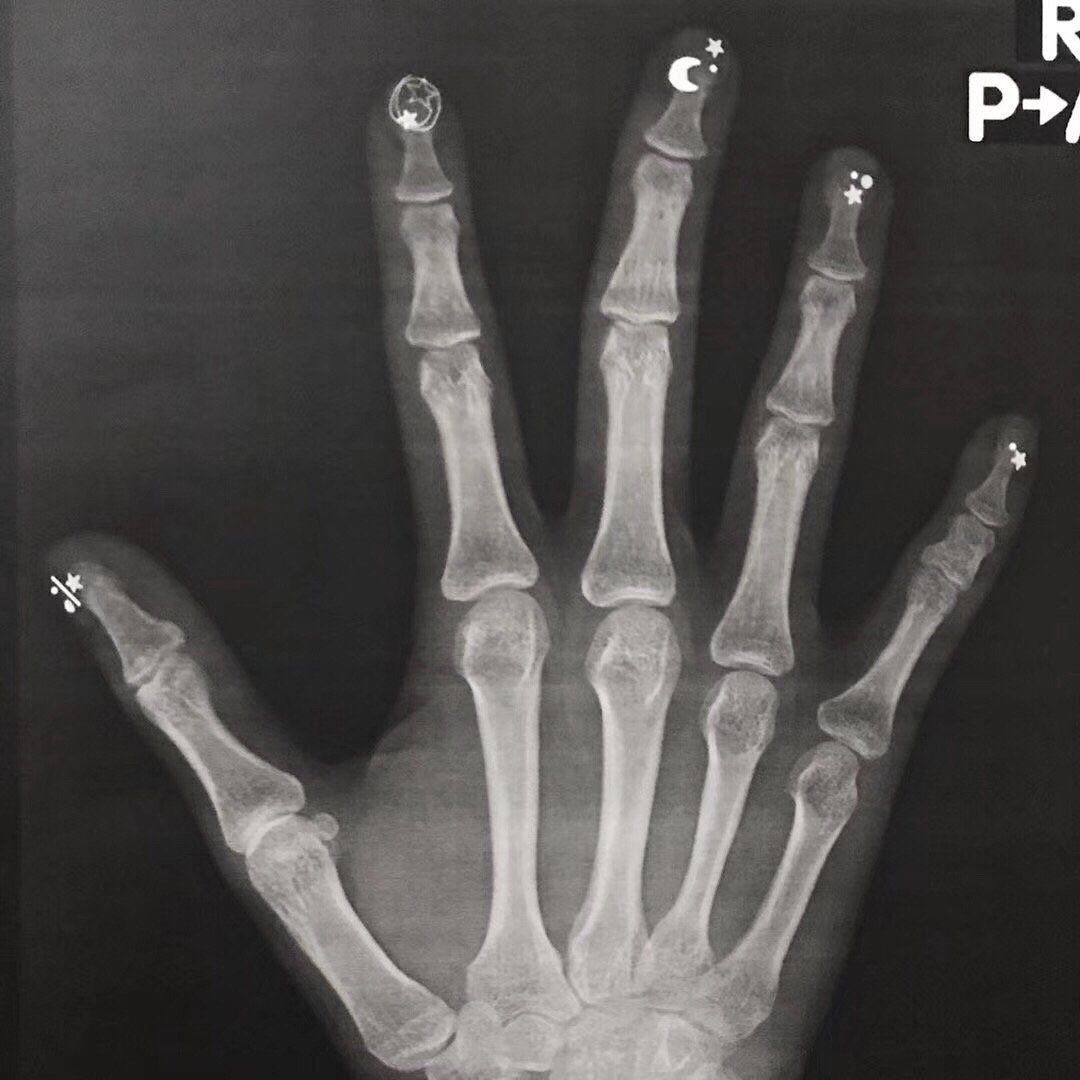

ネイル、気をつけないとレントゲンがファンタジーになる https://t.co/gPrXLTdHDD

— やすいやさん。 (ny1069p) 2019年09月17日

https://pbs.twimg.com/media/EEmE-2BUcAIOEj-.jpg